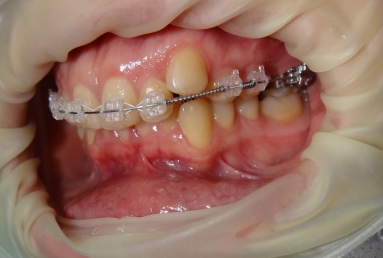

SAPPHIRE ORTHODONTIC DEVICE

Orthodontic treatment, external sinus lifting, dental implant and zirconium crown.